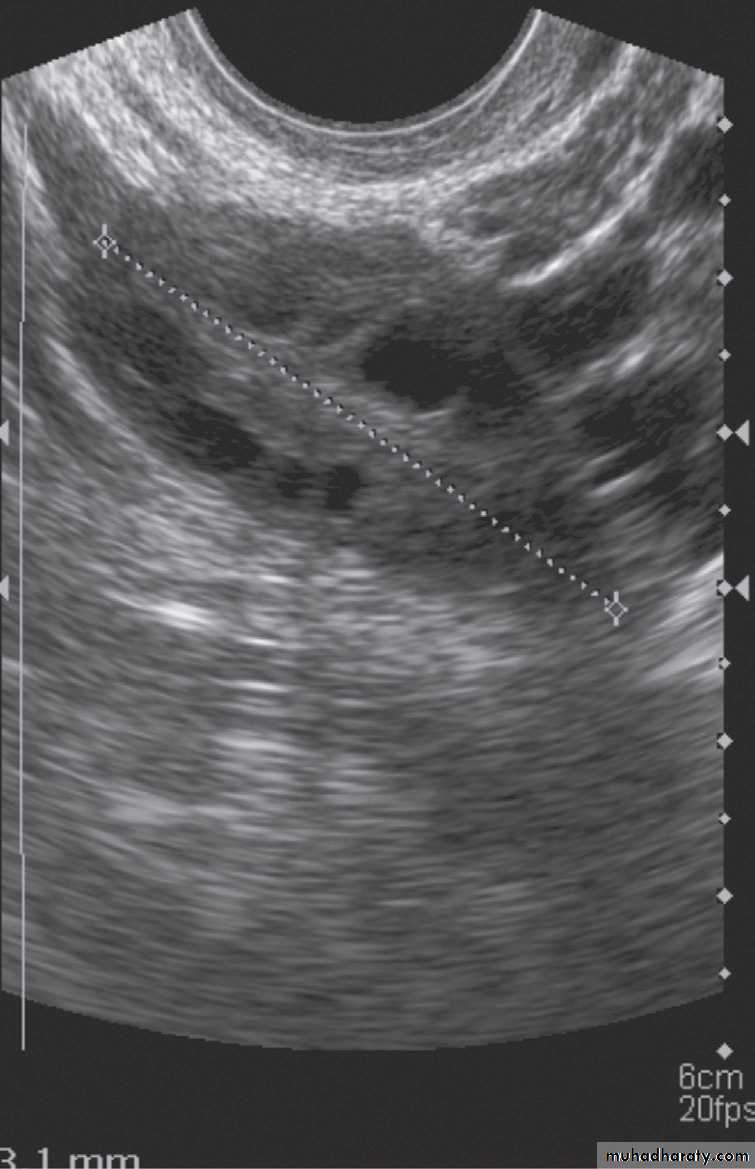

Malignant ovarian masses

• Mixed solid and cystic mass.

• Vascularity within solid components on Doppler.

• Thickened septations, >3 mm.

• Large size.

• Bilateral masses.

• Associated ascites or peritoneal deposits.